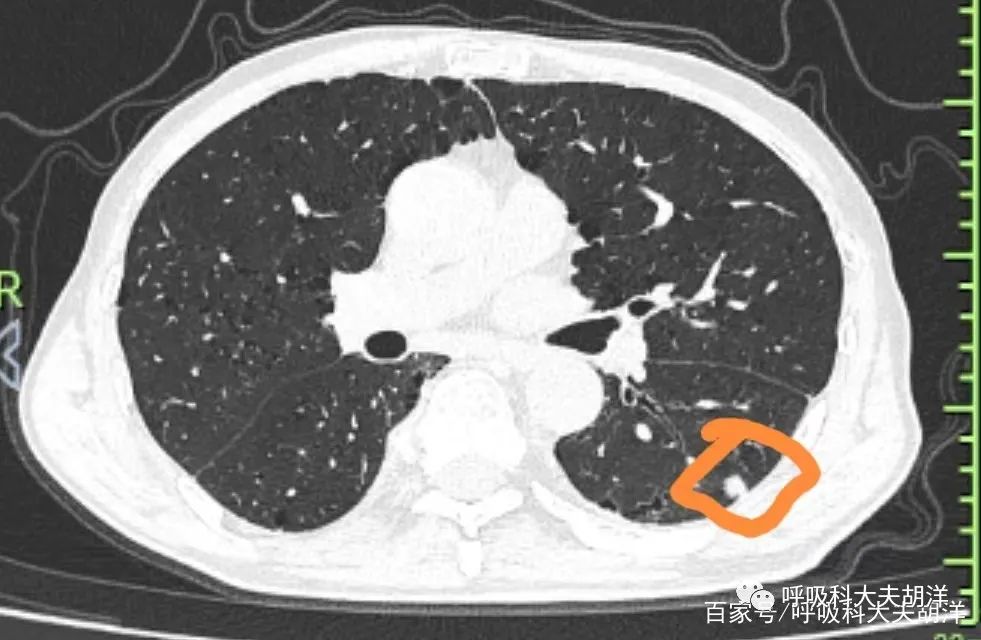

4类(可疑恶性结节)4类结节又细分为4a、4b、4c三类。4a类结节为10-25mm实性结节伴不明确的良性征象。恶性概率为5~15%。处理为:3个月低剂量胸部 CT 筛查;存在≥8mm的实性成分时需 P ET / CT 检查。

4b类结节为持续存在的直径≥10毫米的亚实性密度结节,实性成分≤5毫米。恶性概率>15%。为原位癌或微小浸润癌可能。处理:胸部 CT 增强或平扫靶扫描;根据恶性的概率和并发症,选择性进行PET / CT 和/或组织活检;存在≥8mm的实性成分时,需进行 PET / CT 检查。

4c的恶性率较高,通常为部分实性结节(实性成分≥5mm)在短期随访中无明显改善。直径≥10mm的结节,边界清晰、有分叶及毛刺、无炎症性病变也定义为4C类肺结节。处理方式与4b类相同。